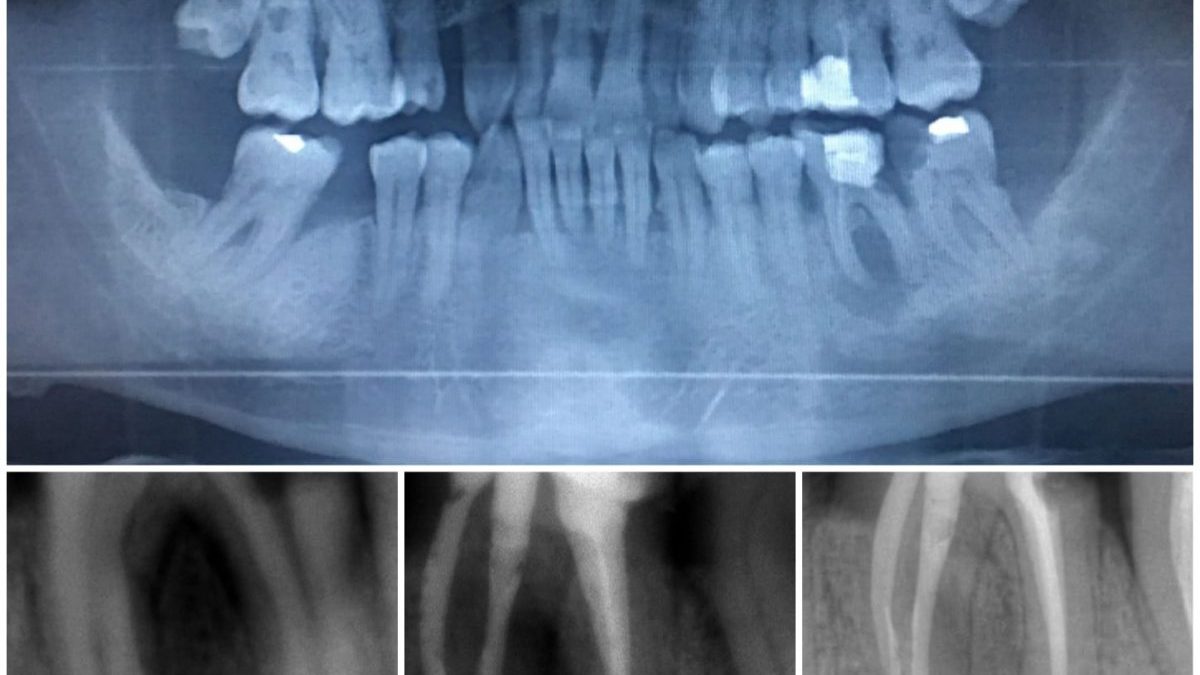

Kanalda Kırılan Eğeye Ne Olacak?

Kök kanal tedavisi esnasında diş hekimlerinin en büyük endişesi kullanılan enstrümanın kanal içinde kırılmasıdır. Peki bu durumun çözümü nedir?

Dişin içinde duran steril bir enstrüman problem yaratmaz ancak varlığından dolayı yeterlidezenfeksiyon yapılamaz ise kanal içinde arta kalan bakterilerden dolayı iltihabı reaksiyon gözlenebilir.

Tablonun biraz daha kritik olduğu durumlar da gözlenebilir; kırılan eğenin kanal dışına itilmesi…

Bu gibi durumlarda prognoz çok iyi olmamakla birlikte hastanın onayı ile dişin kontrol altında tutulması denenebilir. Mümkün mertebe diş çekimi veya cerrahi prosedürler en son seçenek olmalıdır.